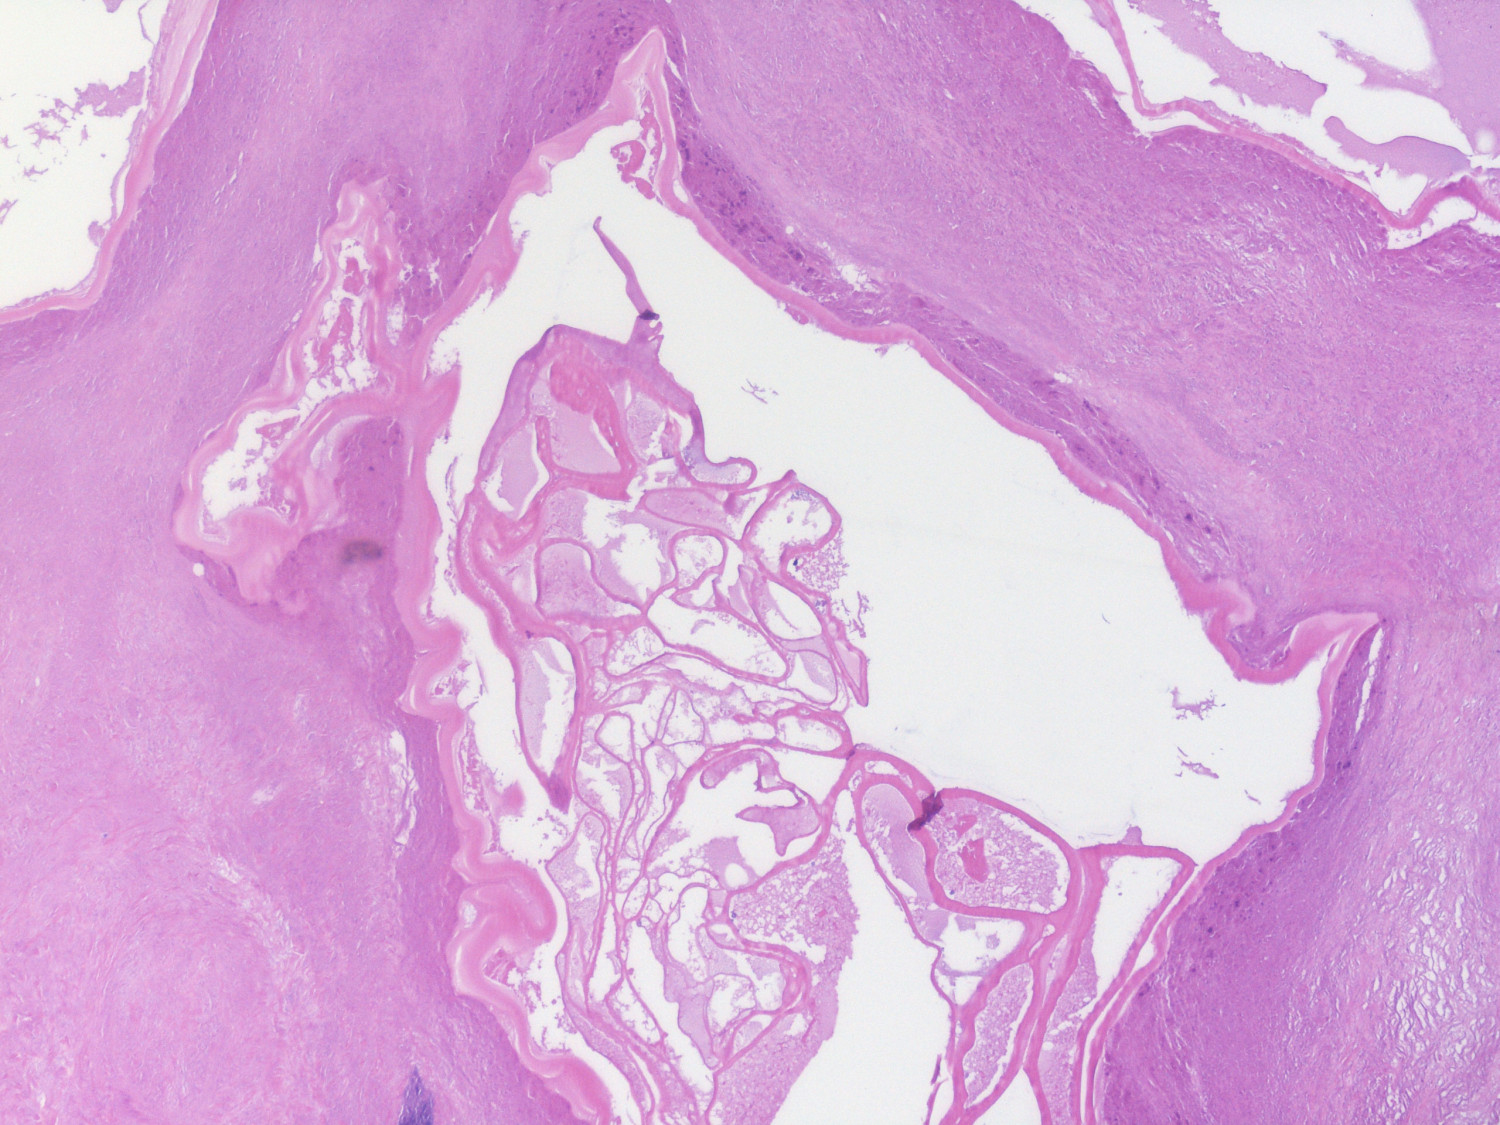

Ved makroskopisk patologisk undersøkelse fremstår lesjonene som multilokulære cystiske kaviteter med nekrose og innhold av tykt, grøtet materiale (figur 2 og 4). Ved mikroskopisk undersøkelse ses cystiske kaviteter med laminerte membraner (figur 5), og i omkringliggende vev ses ulike forandringer som kan inkludere granulomatøs reaksjon, nøytrofile og eosinofile granulocytter, nekrose, fibrose og forkalkning. I motsetning til funn ved infeksjon med E. granulosus, ses ingen germinalmembran eller larver (protoscoleces) (8). Veterinærinstituttet tilbyr PCR-undersøkelse av infisert vev. Instituttet er nasjonalt referanselaboratorium for en rekke zoonotiske smittestoff, og har molekylære verktøy for påvisning og identifikasjon av DNA fra E. multilocularis.